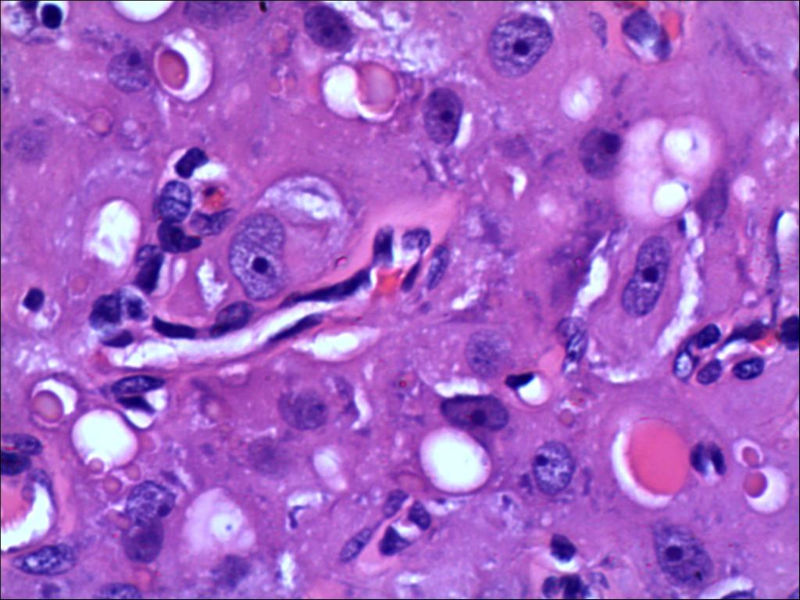

女,27岁,送检右侧卵巢肿物(另外还送检左侧卵巢肿物,大体及镜下显示为畸胎瘤),卵圆形,大小2×1×1cm,似有包膜。卵巢肿物图1

卵巢畸胎瘤中正常卵巢的黄体组织,铺砖样排列,胞浆宽大,较典型。

不好意思,可能是我没说清楚,患者对侧卵巢是畸胎瘤,不是同一侧的,我初步考虑门细胞瘤,图21,22,24,25,26中央的一些细胞是不是很像门细胞

谢谢大家的回答和解疑,忘记一个重要的病史,就是该女性为产妇。但是妊娠黄体瘤与类固醇细胞瘤怎么鉴别呢

那应该是妊娠黄体/黄体瘤,类固醇细胞瘤有嗜酸细胞和组织细胞样细胞两种,此例显然不是。